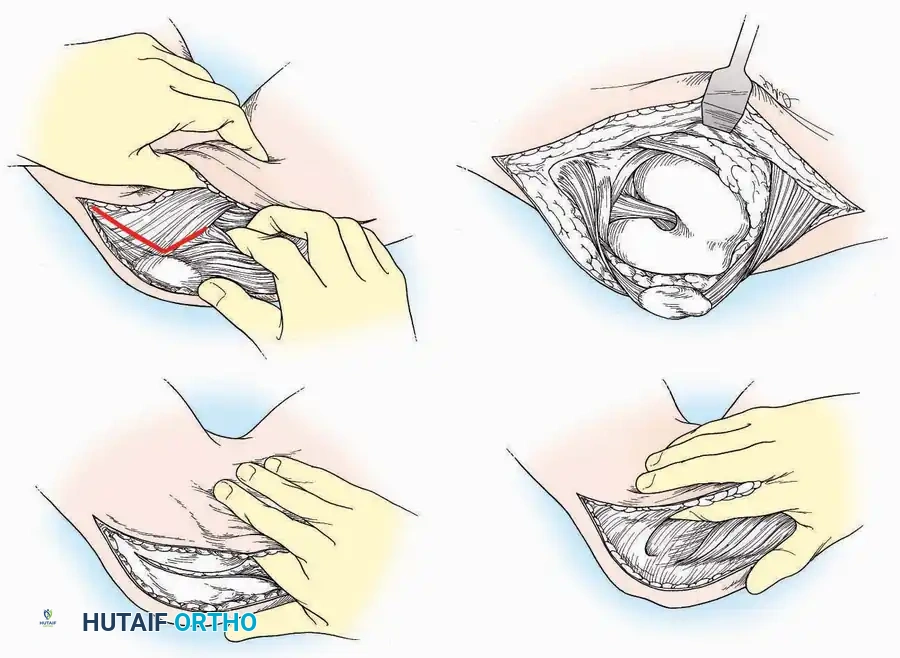

U Approach

Indications: Extensive plantar fasciotomy, radical tumor resection, or complex osteomyelitis debridement requiring access to the entire plantar surface of the calcaneus.

Positioning: Prone, with the leg supported on a large sandbag.

Surgical Technique:

* Incision: Join the medial and lateral approaches described above to form a large, continuous U-shaped incision around the posterior four-fifths of the calcaneus.

* Flap Elevation: Deepen the incision directly to bone. Elevate a massive plantar flap consisting of skin, the specialized fatty heel pad, and the plantar fascia. Retract this flap distally to expose the entire plantar calcaneal tuberosity.

Kocher Approach (Curved L)

Indications: Complete excision of the calcaneus (calcanectomy) for malignant tumors or recalcitrant osteomyelitis.

Surgical Technique:

* Incision: Incise the skin over the medial border of the Achilles tendon, starting 7.5 cm proximal to the calcaneal tuberosity. Extend it distally to the inferoposterior aspect of the tuberosity, curve it transversely around the posterior heel, and continue distally along the lateral surface of the foot to the tuberosity of the fifth metatarsal.

* Deep Dissection: Divide the Achilles tendon directly at its insertion and carry the dissection down to the bone.

* Enucleation: To reach the superior surface, free all tissues beneath the severed Achilles tendon. The calcaneus can then be enucleated subperiosteally or extraperiosteally depending on the oncologic or infectious margins required.